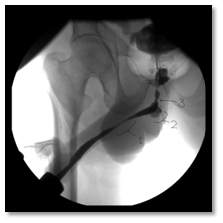

Post-operatively, The SPC was not draining well with persistent suprapubic urine leakage, so the patient was referred to our hospital 2 weeks following the primary surgery. On examination; patient was conscious, well- oriented with average general condition. Abdominal examination showed gapping of suprapubic wound with leakage of turbid urine; the SPC was not functioning well. A stone was felt in the bulbar urethra during perineal examination. Patient gave history of left nephrectomy 2 years before for a nonfunctioning kidney. Serum creatinine, BUN, HB, and WBCs were 64 mg/dl, 3.4 mmol/l , 9.9 gm, and 6640 respectively. Non- contrast CT showed no intraperitoneal fluid collection, right moderate hydroureteronephrosis, dilated left ureter with 2 stones in its lower end and 3 stones in the proximal bulbar urethra (Figure 1). Retrograde urethrocystogram showed a 3 cm stricture segment at the distal bulbar urethra and another annular stricture at the proximal bulbar urethra in addition to an urethral diverticulum in between containing the stone and grade 4 right vesico-ureteral reflux (Figure 2).

Figure 2: Antigradeurethrogram showing (1) distal bulbar uretheral stricture 2.5 cm., (2) urethral diverticulum, (3) proximal bulbar annular stricture.